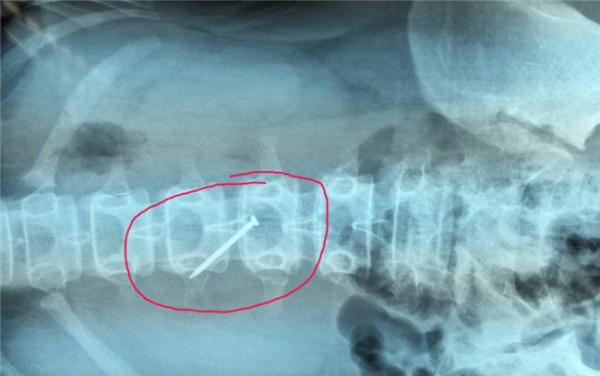

在淮安市妇幼保健院小儿外科的医生办公室里,记者见到了被取出来的铁钉,看上去铁钉已经生锈。从所拍摄的X光片中可以清晰的看出,这根铁钉在取出之前在小轩的胃里的情况。据了解,小轩是泗阳县穿城镇上一所学校的学生,平时寄宿在学校,27日晚,她的父亲突然接到老师的电话称,小轩在学校误吞了钉子,让他们赶紧带小轩去医院看。“我们先是去了镇上的医院,但是拍片子没有拍到,老师又让去县医院看。”小轩父亲告诉记者,到了县医院检查后,钉子确实在肚子里,但是没有技术取出,只能带着孩子辗转到淮安就医,后来他们了解到,女儿是在学校被同学欺负,逼迫吞下铁钉,当时老师发现时,已吞下,他们已向泗阳当地警方报警,目前他们正在查找铁钉来源。

据淮安市妇幼保健院小儿主治医师王挺介绍,28日,当小轩来到该院时,只是表示上腹部稍微有点不适,有恶心的感觉,其他情况还好。通过给她拍片子、检查,医生起初并不认为她有穿孔的迹象。“我们没有贸然选择手术,而是让她留院观察,每隔一段时间拍摄一张X光片。”据王挺介绍,拍摄的多张X光片均显示铁钉一直停留在一个地方没有动。“我们判断这根铁钉极有可能卡在了某个地方或者已经刺破胃壁,没有自己排出的可能性,决定利用腹腔镜手术将铁钉取出。”

通过腹腔镜探查,医生发现在小轩第三腰椎处,钉子尾部穿过胃壁,插在了胆囊和肝脏之间,虽然已经出现了胃穿孔,但是钉子胃部正好将穿孔处完全堵住,没有让胃液和气体淌出来,所以小轩并没有感到非常难受,如果钉子长时间留在肚子里,将可能戳到大血管,危及生命。